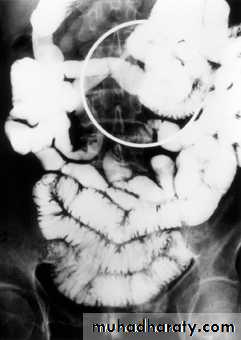

Crohn's disease

It is non-specific granulomatous inflammatory disease of unknown etiology, it nearly always affect the terminal ileum or other several parts of the small and large intestine, leaving normal intervening bowel, forming the skip lesions.The major radiological signs on barium examinations are :

1.strictures(string sign) are variable in length2.contraction of the cecum, this is seen with a diseased terminal ileum

3.dilatation of the bowel may be seen proximal to narrowed areas

4.ulcers :are quite deep. Fine ulceration + mucosal edema=cobblestone appearance

5.thickening,distortion and effacement of mucosal folds

6.separation of loops of bowel due to bowel wall thickening or an inflammatory mass

7.fistula to other loops of SB, colon, bladder or vagina

8.signs of malabsorption